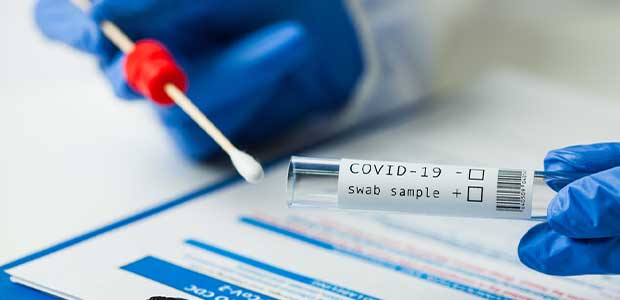

Health experts say it’s important to get tested even if you’re asymptomatic.